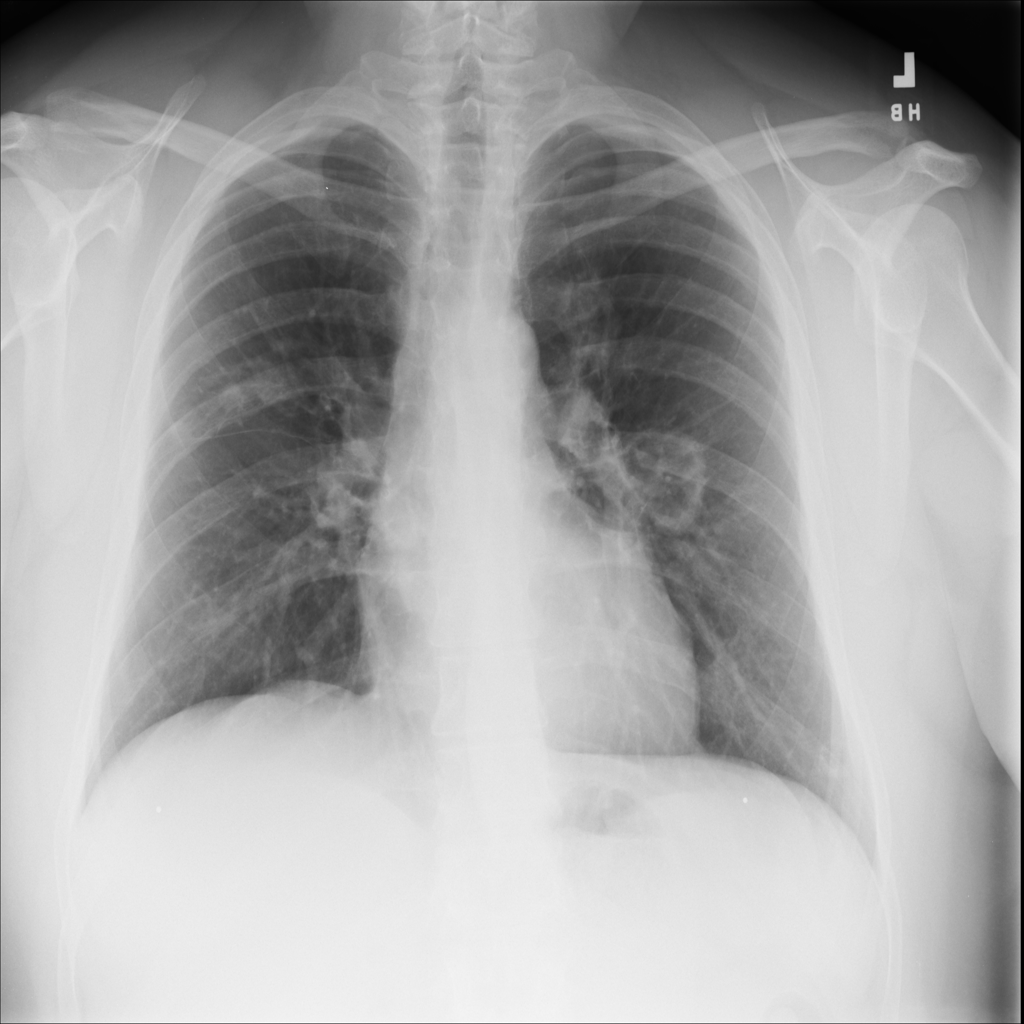

Mass

A mass is a larger focal opacity or lesion seen on the image. It is a descriptive finding that can have several causes and usually needs more imaging or clinical context to characterize.

PAT-4639 · IMG-024Mass

PAT-4639 · IMG-024

AP